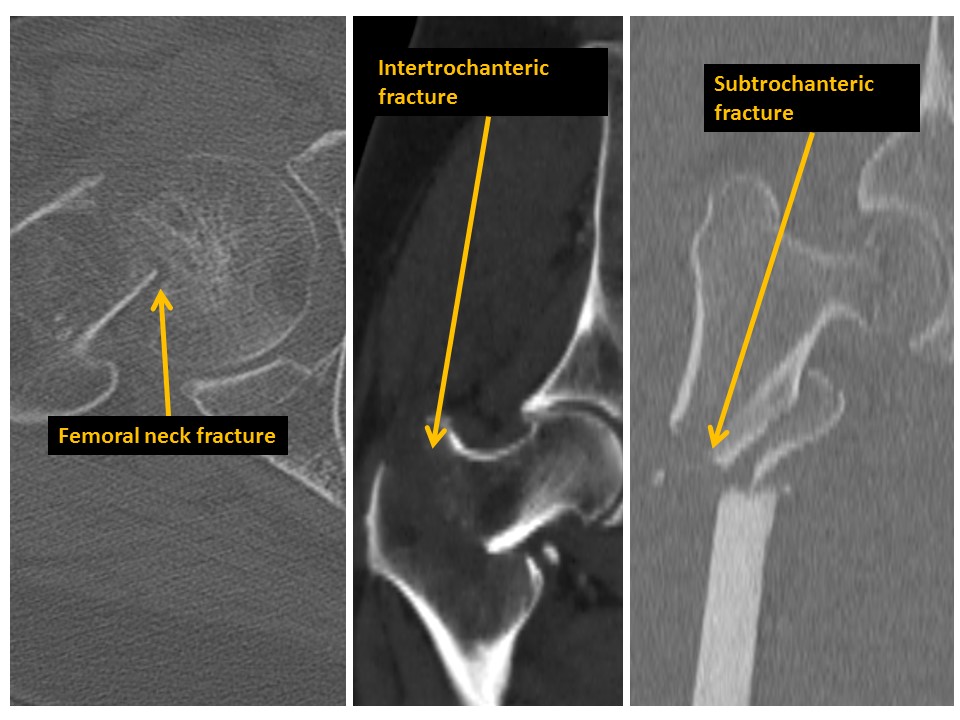

There are fractures of the femoral neck, intertrochanteric region, or subtrochanteric region. [Yes/No]